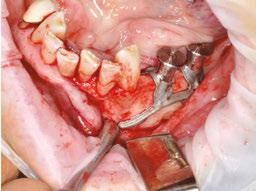

After the soft tissue is prepared, the bony surface is carefully cleaned. For easy insertion, the healing abutments are left in place, and the implant is held firmly with hemostatic forceps (Figure 7). The implant is inserted via distal translation in the direction of the angle of the mandible, then a mesio-anterior rotation. The surgeon must control the lack of mobility and the adaptation of the implant to the bony surface at all points (Figures 8A, 8B, 8C, and 8D).

To ensure the implant is stable during the osseointegration period, an osteosynthesis screw is placed in the prepared space (Figures 9A, 9B, 9C, and 9D).

The flaps are carefully repositioned and sutured without tension with Halsted and over-and-over sutures (Figures 10A and 10B).

Figures 8A-8D: Placing the subperiosteal implant and monitoring its adaptation Figures 5A and 5B: 5A. Initial clinical view. 5B. Access flap Figure 6: Periosteal expansion using a soft brush Figure 7: Prehension of the subperiosteal implant